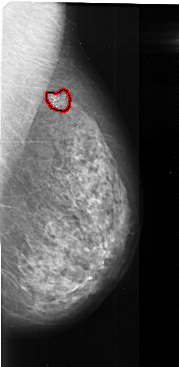

A_1023_1.RIGHT_CC

RIGHT_MLO LINES 5491 PIXELS_PER_LINE 2671 BITS_PER_PIXEL 16 RESOLUTION 42 OVERLAY

FILE: A_1023_1.RIGHT_MLO.OVERLAY

TOTAL_ABNORMALITIES 1

ABNORMALITY 1

LESION_TYPE CALCIFICATION TYPE FINE_LINEAR_BRANCHING DISTRIBUTION CLUSTERED

ASSESSMENT 5

SUBTLETY 5

PATHOLOGY MALIGNANT

TOTAL_OUTLINES 1

BOUNDARY